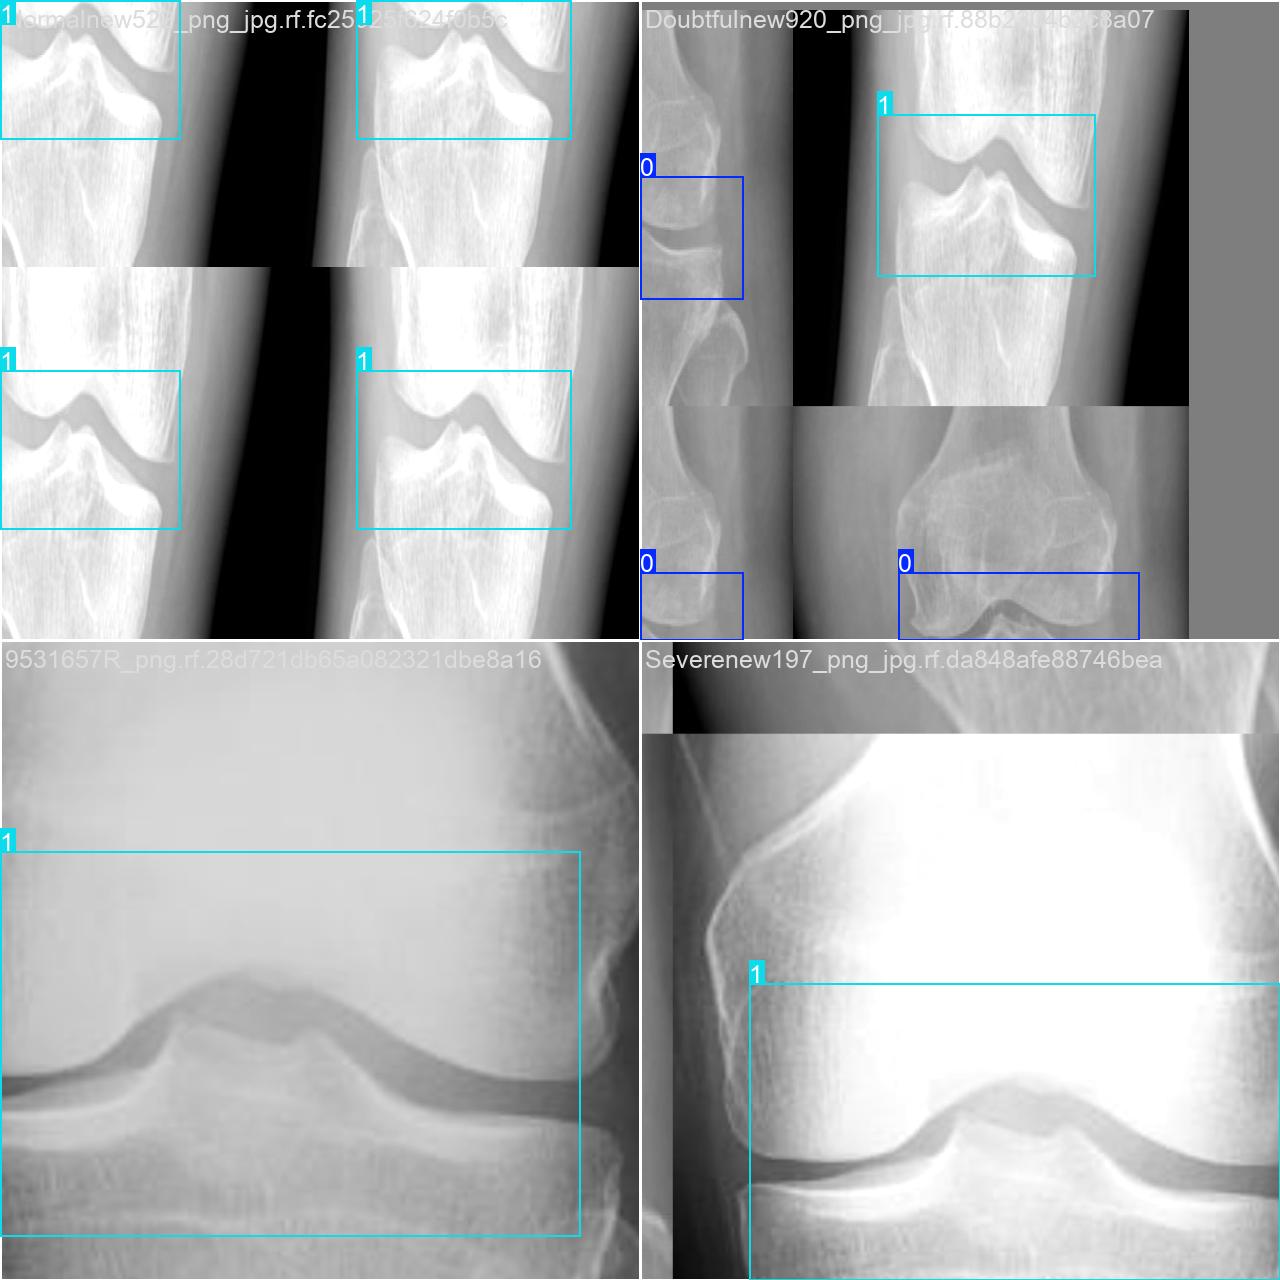

部分数据集图像如下图所示:

部分标注如下图所示:

2.数据集准备与训练

本研究使用了包含骨折情况的数据集,并通过 Labelimg 标注工具对每张图像中的目标边界框(Bounding Box)及其类别进行标注。基于此数据集,采用 YOLOv8n 模型进行训练。训练完成后,对模型在验证集上的表现进行了全面的性能评估与对比分析。整个模型训练与评估流程包括以下步骤:数据集准备、模型训练、模型评估。本次标注的目标类别主要集中于骨折情况。数据集总计包含 29126 张图像,具体分布如下:

训练集:5600 张图像,用于模型学习和优化。

验证集:1600 张图像,用于评估模型在未见过数据上的表现,防止过拟合。

测试集:800 张图像,用于最终评估模型的泛化能力。